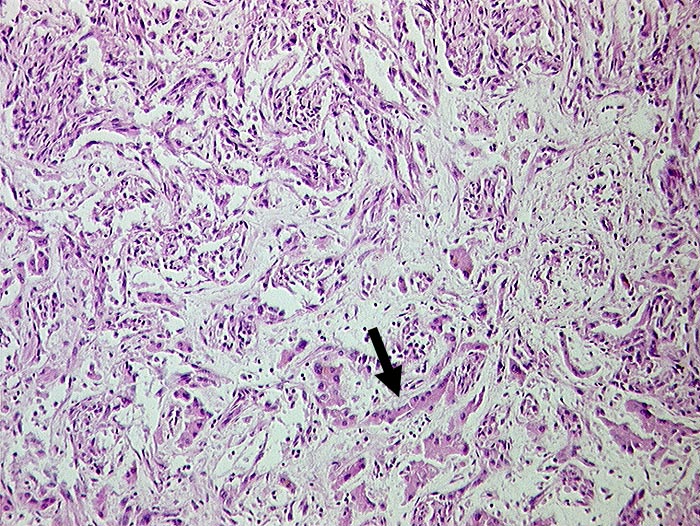

AP/ Angiosarkom der Leber

Angiosarkom der Leber

Pathologischer Befund